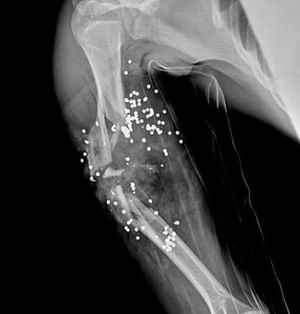

X - ray for a right arm after gun shot